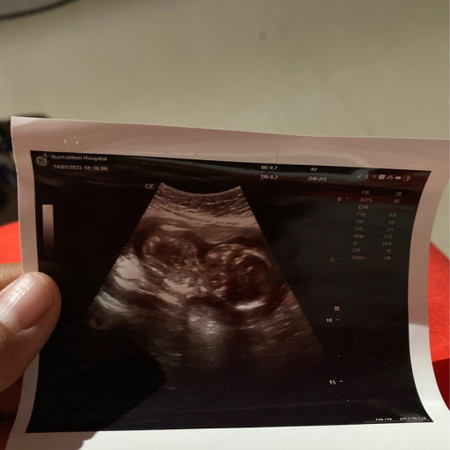

19+1 อัลตราซาวด์ล่าสุด

น้องอายุครรภ์ 19+1 ภาพซาวด์ล่าสุด ส่วนที่ป๋องลงมาจากคอ คือ ท้องน้องไหมคะ ปกติดีใช่ไหมคะ เห็นมันโตจัง

ใช้คะ ปกติ เด็กอยุ่ในท้องจะนอนขดๆตัวคะ